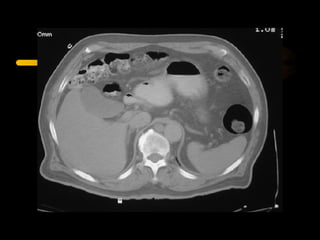

La tomografía computada fue desarrollada por Sir Godfrey Hounsfield y Allan Cormack, quienes recibieron el Premio Nobel de Fisiología o Medicina en 1979 por su trabajo pionero en la aplicación de la computación para generar imágenes transversales del cuerpo humano. La tomografía computada utiliza rayos X y computadoras para crear imágenes transversales del cuerpo.